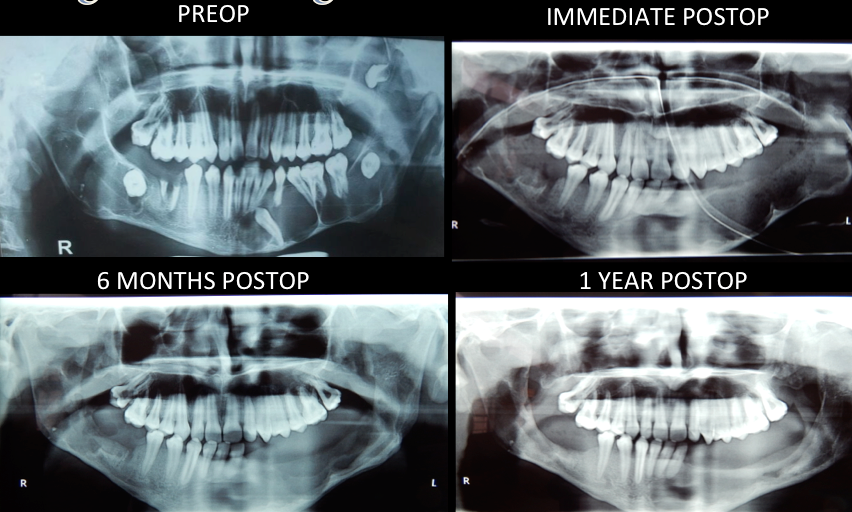

Tumors and Cysts of Jaw and Face

Other than cancer, there are malignant and benign lesions that develop in oral and dental tissues. These could be associated to teeth or may be not.

These conditions are morphologically and functionally disturbing. Treatment of these conditions are Surgical and can be taken careoff if recognised early.

Consult oral and maxillofacial surgeon